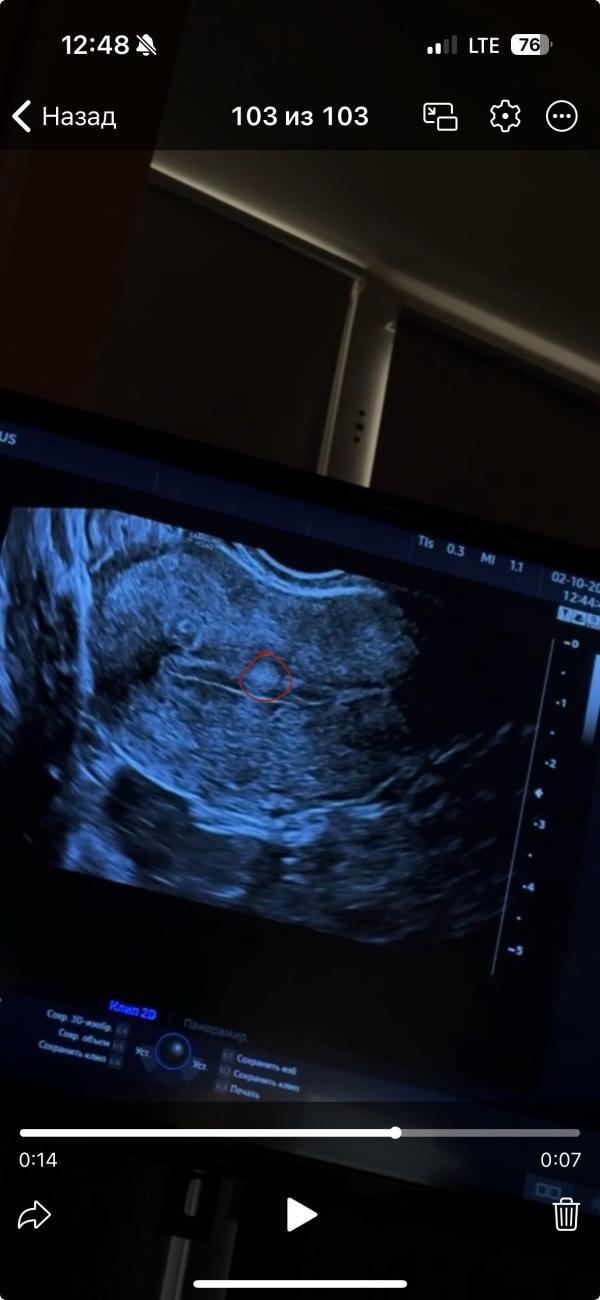

Что может быть на эндометрии после пункции фолликулов

Женсовет, что это может быть на эндометрии?

Кровотока нет, узист сомневается, что это полип

1 Цикл после пункции фолликулов

Это полип

Полип скорее всего, что это еще может быть